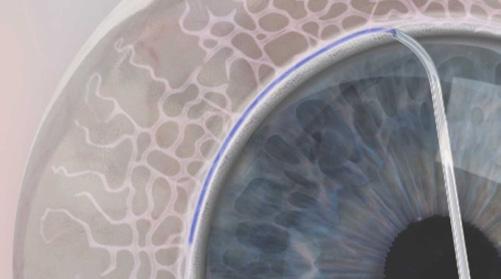

Le dispositif OMNI est facilement inséré dans la chambre antérieure, par une incision cornéenne claire de 1 mm (Figure 1), avec un embout de canule courbé rempli d’un OVD de haut poids moléculaire tel que Healon GV (Johnson & Johnson Vision) ou similaire. Une lentille gonio avec ou sans poignée est placée sur la cornée pour permettre une visualisation correcte de l’angle. L’extrémité de la canule est ensuite déplacée à travers la pupille, vers l’angle iridocornéen, et l’extrémité de la canule est pressée contre le réseau trabéculaire (RT) pour créer une petite ouverture dans le canal de Schlemm. Le microcathéter est ensuite inséré en tournant la petite roue située sur la poignée du dispositif (Figure 2). Une fois le microcathéter rétracté, l’OVD est injecté en quantité constante et mesurée pour dilater le canal de Schlemm et traiter les éventuelles hernies ou blocages des canaux collecteurs distaux107

La nouvelle série Ergo optimise l’ergonomie et la facilité d’utilisation chirurgicale tout en permettant aux chirurgiens d’effectuer des procédures de glaucome peu invasives et sans implant108